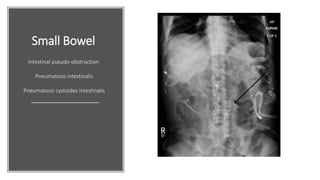

Small Bowel

Intestinal pseudo-obstruction

Pneumatosis intestinalis

Pneumatosis cystoides intestinalis